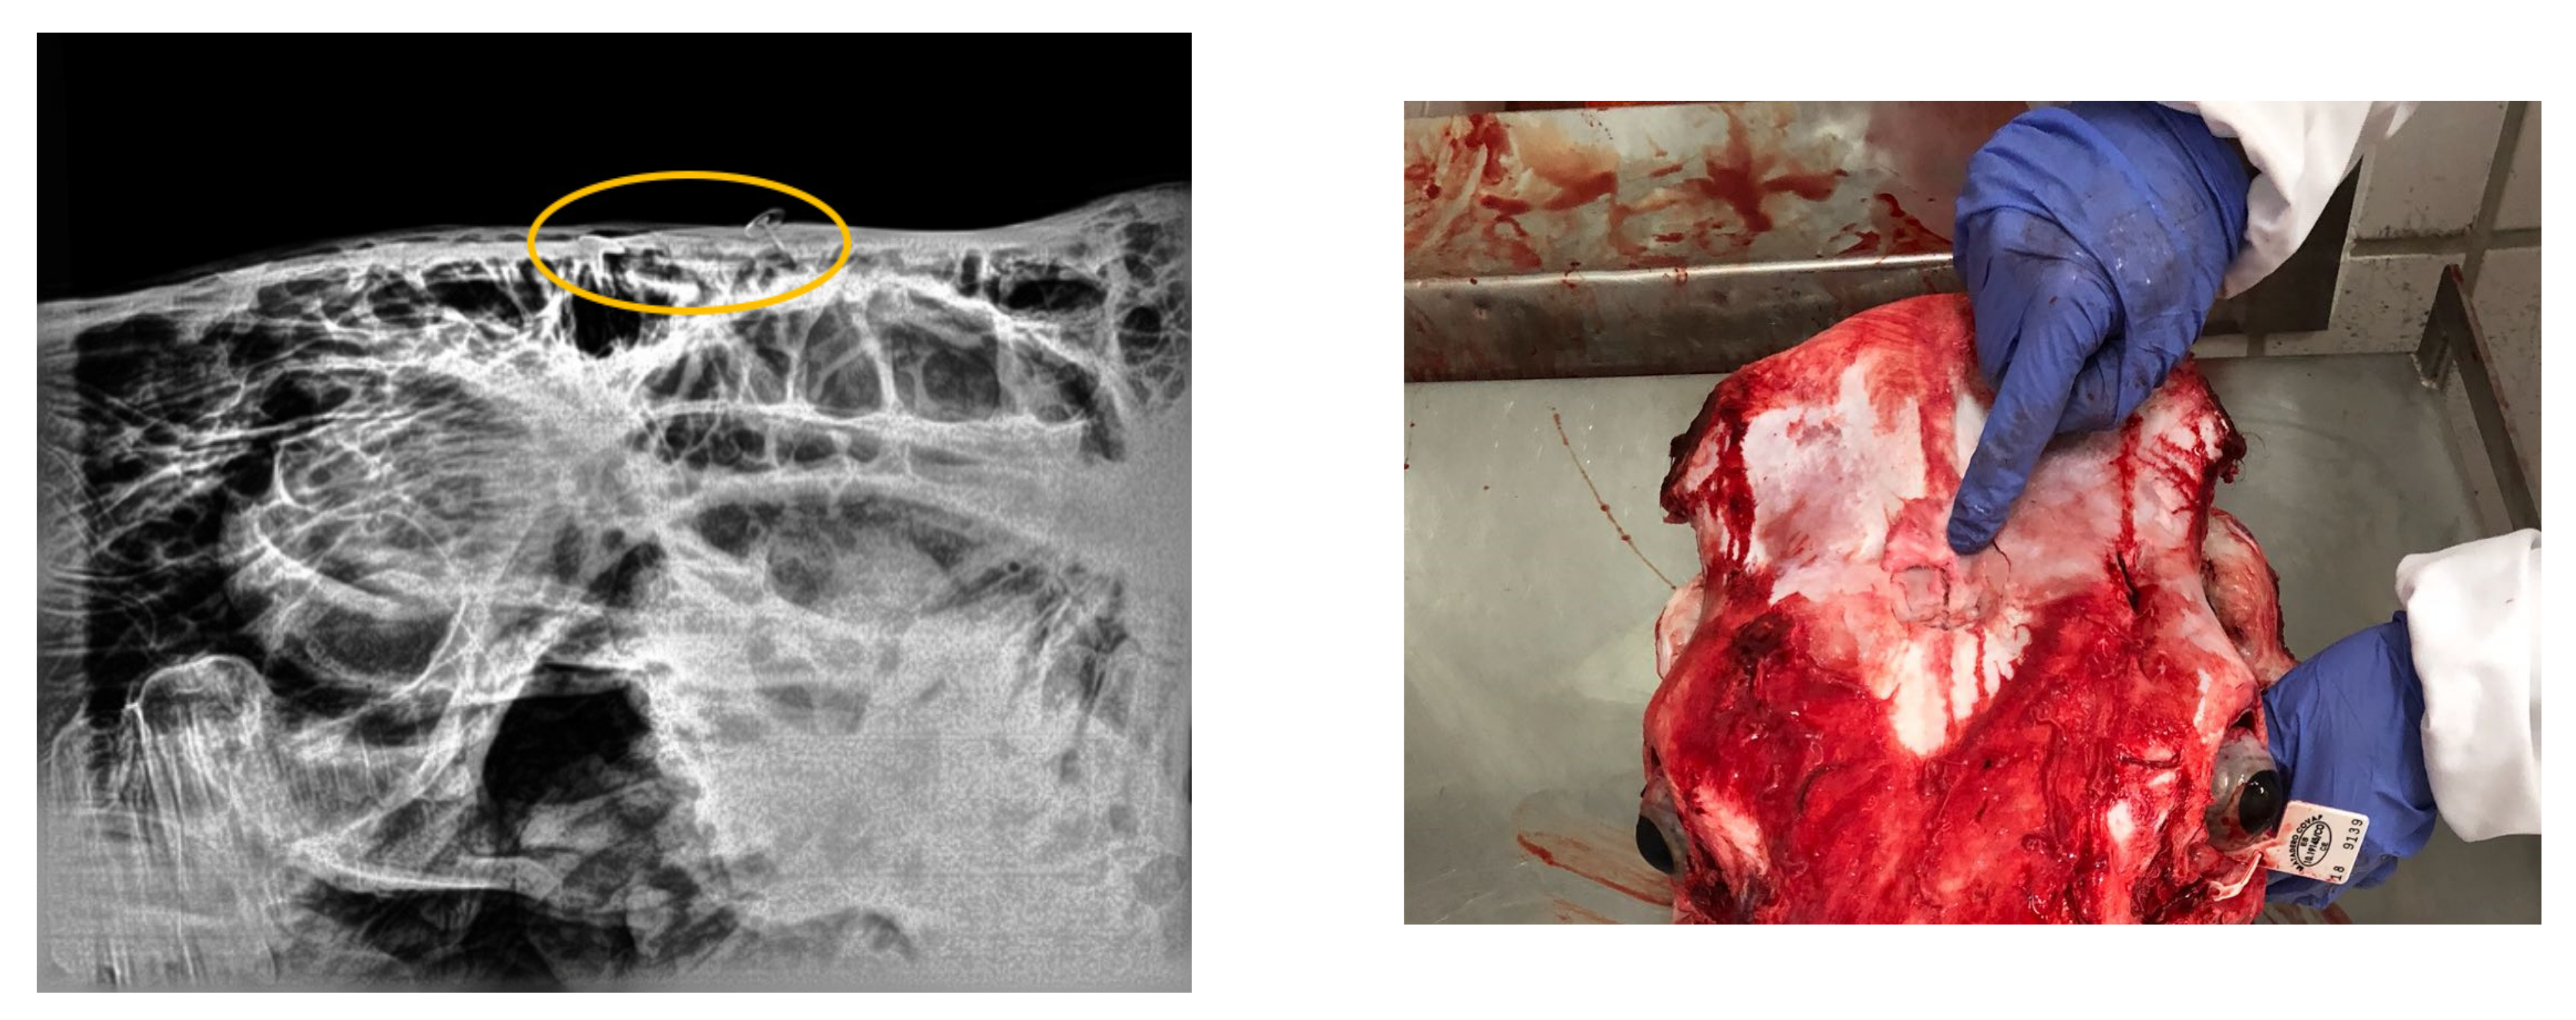

Regarding the radiographical study, it was observed that the skulls presented rating 1 “no visible damage” (70%) or 2 “indentation no cracking” (20%), and rating 3 “indentation with cracking but no displacement” (10%) following the Malaysia Standard (Figure 3, Figure 4, Figure 5). Consequently, 90% of the HSS animals (ratings 1 and 2) would be accepted for halal commercialization. However, no radiographical differences existed between ratings 1 and 2 (Figure 3 and Figure 4); only macroscopic differences in soft tissues were noted.

Figure 3. Digital radiography rating 1 (following Malaysia Standard 1500:2009), and related photograph.

Figure 4. Digital radiography rating 2 (following Malaysia Standard 1500:2009), and related photograph.

Figure 5. Digital radiography rating 3 (following Malaysia Standard 1500:2009). The eclipsed area defines the perimeter of the damaged area. On the right is shown the related photograph.

2.4. Methodology of Radiographic Study

Digital radiographs of the lateral head were obtained on beef cattle stunned by the non-penetrative captive bolt (10 HSS samples), to determine the skull damage of the forehead of the animal, according to Appendix A2 of Malaysian Protocol [22] for the Halal Meat and Poultry Productions (MS-1500:2009). A standard approach for radiographic examination (PotroDR1®, CVM, Metron Software) was used. For each region, a minimum of 3 standard views were obtained, with 72 MHz and 20 MAs. The macroscopic damage in the frontal bone was observed.

As Majeed et al. [37] exposed, a beating heart is indispensable for a thorough bleed-out by the animal and attainment of a higher amount of blood at exsanguination is better during halal slaughter according to Shari’ah (halal law). Even if the variation in Islamic jurisprudence is one of the primary determinants of intra-regional trade of halal meat import demand in OIC member countries [38], most certifiers indicate that they accept pre-slaughter stunning if the stunning does not result in the death of animal prior to exsanguination, a Muslim should perform the slaughter and a short prayer must be recited and only manual (by hand) slaughter is acceptable [39]. According to this premise, our findings revealed the halal slaughter with stunning was the best procedure from the microbiological and AW point of view. At present, the Malaysian Protocol for the Halal Meat and Poultry Productions allows the non-penetrative captive bolt stunning for bovine [22] setting a rating scale of 6 grades depending on the skull damage. The radiological study in our research demonstrates the benefits of this stunning method in the tested animals, evidencing the ratings 1 or 2 for 90% of the skulls; this means the halal condition for the carcass.